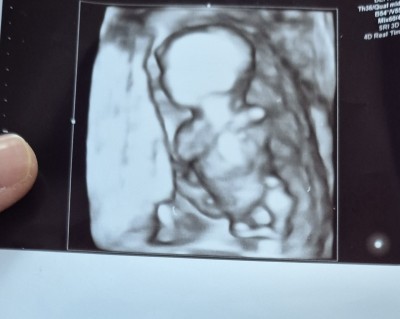

13 hafta 4 gunluk sizce cinsiyet nedir anlayan varmi doktor bi tahminde bulundu ama hafta erken oldugu icin kesinlik vermedi.

Gebelik haftası 13+4

erkek gibbiiii

Erkek gibi baya belli ama

Valla canm bende erkek olarak gördüm orasına doğru bakın sizde fark edeceksiniz kız erkek fark etmiyor gerçekten sağlıkla gelsinler 👣❤️

Net erkek bence hayırlısı olsun